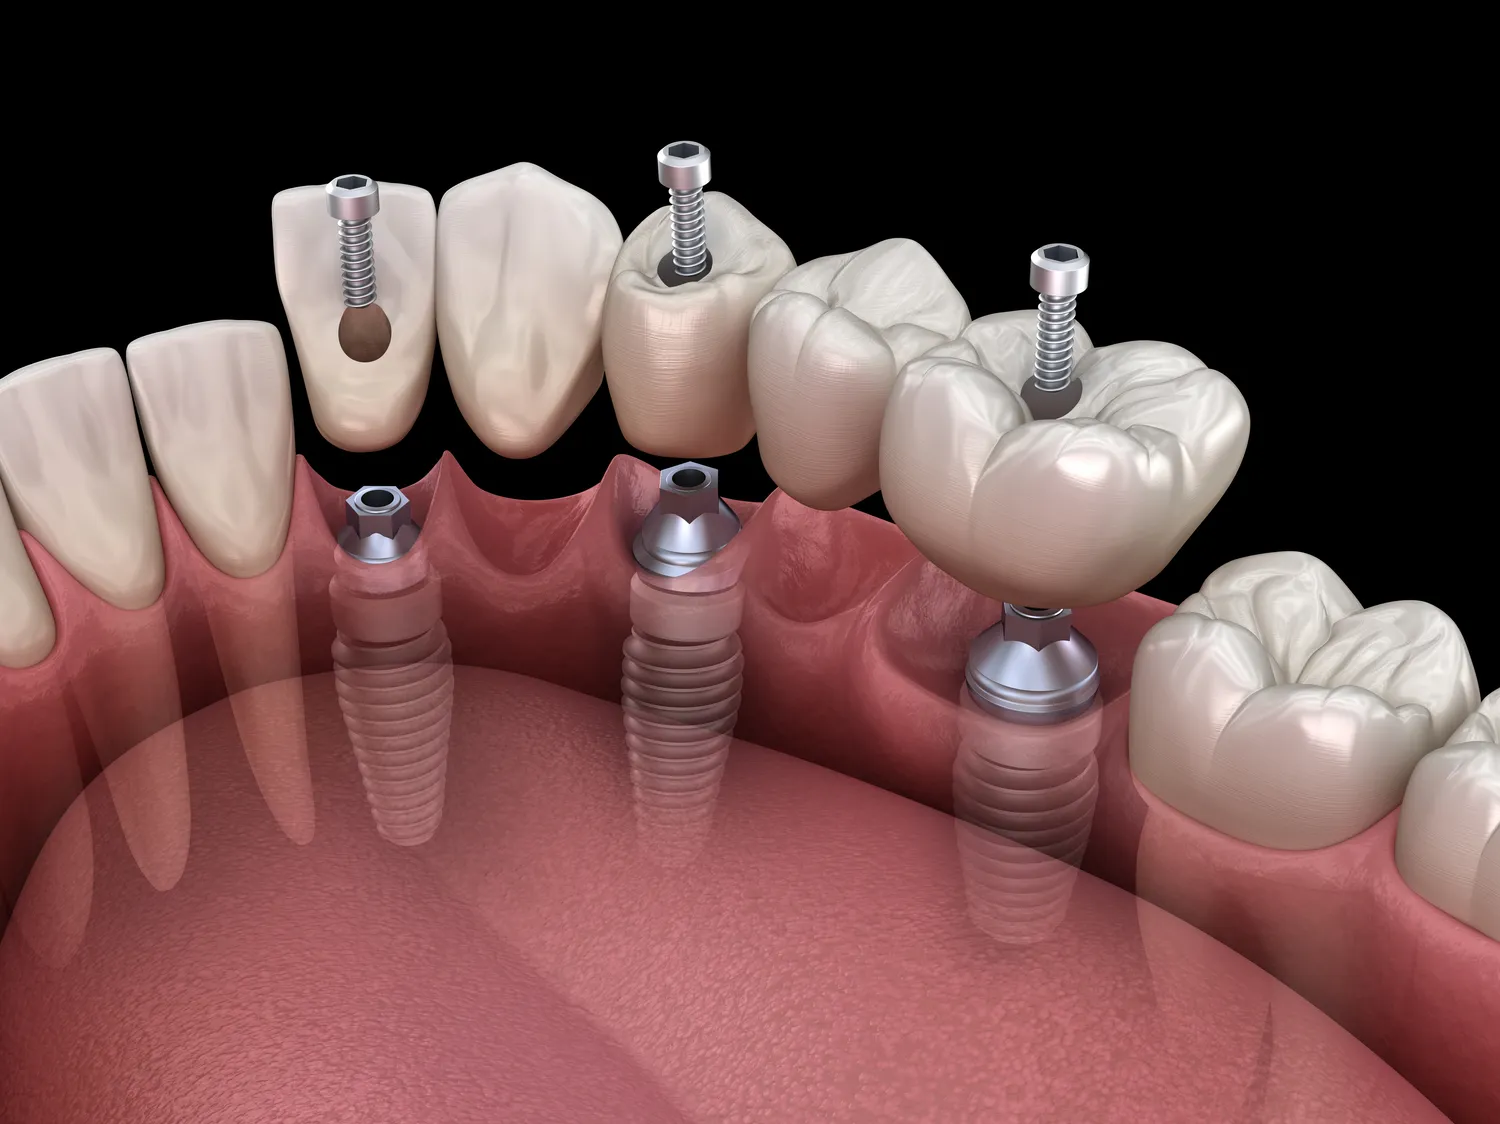

Leczenie zębów w jeden dzień to innowacyjna metoda, która zyskuje na popularności w Koszalinie. Dzięki nowoczesnym technologiom oraz zaawansowanym procedurom dentystycznym pacjenci mogą cieszyć się pięknym uśmiechem już po jednej wizycie. Proces ten zazwyczaj rozpoczyna się od dokładnej diagnostyki, która obejmuje zdjęcia rentgenowskie oraz szczegółowe badania jamy ustnej. Dentysta ocenia stan zębów i dziąseł, a następnie przedstawia pacjentowi plan leczenia. W przypadku konieczności usunięcia zębów lub przeprowadzenia implantacji, wszystkie te zabiegi są wykonywane w tym samym dniu. Dzięki zastosowaniu technologii CAD/CAM możliwe jest szybkie zaprojektowanie i wykonanie koron czy mostów protetycznych, co znacznie przyspiesza cały proces.

Leczenie zębów w jeden dzień w Koszalinie opiera się na zastosowaniu nowoczesnych technologii, które znacznie zwiększają efektywność i komfort zabiegów. Jednym z kluczowych elementów jest technologia CAD/CAM, która umożliwia cyfrowe projektowanie i produkcję uzupełnień protetycznych. Dzięki temu dentysta może szybko stworzyć model zęba, a następnie wykonać koronę czy most w ciągu kilku godzin. To znacząco skraca czas oczekiwania na gotowe uzupełnienie, co jest szczególnie ważne dla pacjentów pragnących uniknąć wielokrotnych wizyt. Kolejnym istotnym narzędziem jest tomografia komputerowa, która pozwala na dokładną ocenę struktury kości oraz lokalizacji nerwów, co jest niezbędne przy planowaniu implantacji. Dzięki temu lekarze mogą precyzyjnie zaplanować zabieg, minimalizując ryzyko powikłań. Warto również wspomnieć o laserach dentystycznych, które są coraz częściej wykorzystywane do leczenia chorób dziąseł oraz przeprowadzania zabiegów chirurgicznych.